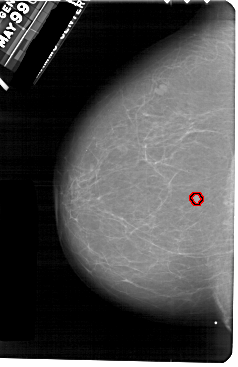

ics_version 1.0 filename A-1754-1 DATE_OF_STUDY 9 5 1996 PATIENT_AGE 59 FILM FILM_TYPE REGULAR DENSITY 1 DATE_DIGITIZED 16 3 1999 DIGITIZER HOWTEK 43.5 SEQUENCE LEFT_CC LINES 5491 PIXELS_PER_LINE 3556 BITS_PER_PIXEL 12 RESOLUTION 43.5 OVERLAY LEFT_MLO LINES 5341 PIXELS_PER_LINE 3361 BITS_PER_PIXEL 12 RESOLUTION 43.5 OVERLAY RIGHT_CC LINES 4996 PIXELS_PER_LINE 2956 BITS_PER_PIXEL 12 RESOLUTION 43.5 NON_OVERLAY RIGHT_MLO LINES 5281 PIXELS_PER_LINE 3226 BITS_PER_PIXEL 12 RESOLUTION 43.5 NON_OVERLAY |

FILE: A_1754_1.LEFT_MLO.OVERLAY TOTAL_ABNORMALITIES 1 ABNORMALITY 1 LESION_TYPE MASS SHAPE ROUND MARGINS CIRCUMSCRIBED ASSESSMENT 3 SUBTLETY 4 PATHOLOGY BENIGN TOTAL_OUTLINES 1 BOUNDARY |